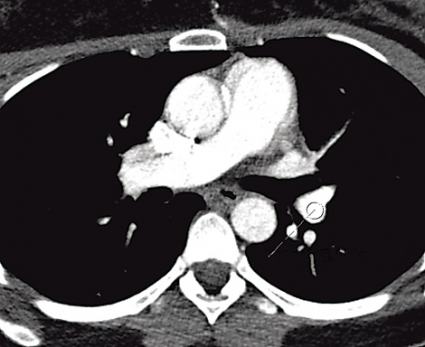

Lungröntgen. Det går inte att med lungröntgen vare sig specifikt påvisa LE eller skilja mellan ischemiska och pneumoniska parenkymförtätningar [44]. Undersökningen kan dock vara av värde för differentialdiagnostik (till exempel pneumotorax, massiv pleurautgjutning och lungödem) innan man går vidare med DTLA och för bedömning av skintigrafi [3, 7, 45, 46]. Lungröntgen ger minimal stråldos till både moder (medeltal Sverige 2006: 0,07 mSv) [47] och foster (<0,01 mGy) [32]. Lungskintigrafi. En systematisk litteraturgenomgång år 2006 avseende bilddiagnostik av LE hos gravida [9] fann endast en retrospektiv skintigrafistudie [48] som motsvarade de uppsatta kvalitetskriterierna med bland annat uppföljning av patienter med negativt test. Ytterligare en retrospektiv skintigrafistudie (n = 97) publicerades 2007 [49]. Skintigrafifynden i dessa två studier bedömdes som normala hos 172 (81,9 procent), icke-diagnostiska hos 35 (16,7 procent) och förenliga med hög sannolikhet för LE hos 3 (1,4 procent) patienter. Sex kvinnor med normalt (n = 2) eller icke-diagnostiskt (n = 4) fynd fick antikoagulationsbehandling på klinisk grund. Övriga med icke-diagnostisk (n = 31) eller normal (n = 170) skintigrafi hade ingen episod av VTE under 20–25 månaders medeluppföljning. Icke konklusiva skintigrafifynd vidareutreds i första hand med DTLA. Om inte heller DTLA är konklusiv görs ultraljud avseende DVT i nedre extremiteterna. Ett normalt bilateralt ultraljud av hela benet, eller seriellt proximalt ultraljud dag 1, 3 och 7 i kombination med icke-diagnostisk skintigrafi, utesluter med hög sannolikhet behandlingskrävande VTE hos icke-gravida [3]. I tidig graviditet är det viktigt att vara medveten om ökad förekomst av DVT i övre extremiteter och v jugularis i samband med assisterad befruktning [50]. Skintigrafi utförs på de flesta av landets sjukhus med konventionell planar teknik, ofta tolkad utifrån reviderade probabilistiska kriterier [51] byggda på PIOPED I-studien (prospective investigation of pulmonary embolism diagnosis), och med relativt hög andel icke konklusiva undersökningar [52]. Med modern skintigrafi (SPECT, single photon emission tomography) kan antalet icke konklusiva undersökningar reduceras till 1–3 procent [53-55]. I nya rekommendationer för diagnostik av LE föreslås SPECT vara förstahandsmetod också för gravida [21, 22]. Enligt dessa och andras rekommendationer [7, 19, 20] utförs skintigrafi hos gravida primärt endast med perfusion och med reducerad aktivitet (cirka 50 MBq), oavsett om planar skintigrafi eller SPECT används. I de relativt få fall som perfusionsskintigrafin är patologisk kompletteras med ventilationsskintigrafi nästa dag för att säkerställa diagnosen. Datortomografi av lungartärer. Hos icke-gravida, men inte hos gravida, finns evidens för att normal DTLA med hög säkerhet utesluter behandlingskrävande VTE [56, 57]. Nyligen publicerades två artiklar som uppmärksammade kända brister i diagnostisk kvalitet för DTLA hos gravida [13, 15], vilka huvudsakligen berodde på för låg kontrasttäthet i lungartärerna sekundärt till ökad hjärtminutvolym [58] under graviditet [59]. Man kan alltså inte använda injektionsprotokoll för icke-gravida på gravida. Gravida kräver högre kontrastmedelsdoser och/eller injektionshastigheter [14]. Analys visar att med studiernas [13, 15] injektionsparametrar varierade doshastigheten mellan 15 och 23 mg jod per kg och sekund vid en vikt på 60–80 kg. Enligt vår erfarenhet krävs det cirka 30 mg jod per kg och sekund på gravida för att kontrasttätheten i lungartärerna ska bli tillräcklig (Figur 1, Tabell V). Patienten bör noga instrueras att hålla andan utan valsalvamanöver och undvika djup inandning [14, 60]. MRT av lungartärerna har i dag ingen etablerad plats i diagnostiken av LE. Sammanfattning Evidens saknas angående val av bästa strategi vid diagnostik av LE hos gravida. Vid val av bilddiagnostisk metod måste man vid varje sjukhus ta hänsyn till tillgänglig metodik, expertis, lokala erfarenheter och vilken diagnostisk kvalitet och stråldos metoderna levererar. Strålsäkerhetsmyndigheten föreskriver specifikt för gravida att de »ska undersökas med utrustning och metod som ger en så låg stråldos till fostret som är rimligt möjligt. Valet skall dock göras så att den nödvändiga diagnostiska informationen erhålls« (SSMFS 2008:31). Skillnader i stråldos mellan skintigrafi med halverad aktivitet och DTLA är enligt Tabell IV större för modern än för fostret. Risken för strålinducerad letal cancer är störst för modern efter DTLA även om stråldoserna vid DTLA optimeras enligt förslag i Tabell V. Risken med stråldoserna vid skintigrafi och DTLA för den enskilda modern och fostret måste dock anses som negligerbar jämfört med konsekvenser av både under- och överdiagnostik av LE. Vi rekommenderar perfusionsskintigrafi (halverad aktivitet) som förstahandsmetod för diagnostik av LE hos gravida på grund av hög andel konklusiva undersökningar, lägre stråldos till modern (speciellt till den proliferativa bröstvävnaden, som kan vara extra känslig för joniserande strålning under graviditet och särskilt vid kända riskfaktorer för att utveckla bröstcancer), inga kontrastmedel och viss osäkerhet vad gäller DTLA:s diagnostiska kvalitet [61]. Vid misstanke om LE hos unga icke-gravida kvinnor kan skintigrafi också vara att föredra som förstahandsmetod på grund av den lägre stråldosen till bröstkörtlarna. Varje sjukhus bör ha en dokumenterad utredningsplan för gravida med misstänkt LE, och man bör optimera stråldoserna vid skintigrafi och DTLA samt kontrastmedelsprotokollen vid DTLA. Varje gravid kvinna ska ha rätten att få korrekt information om typ och magnitud av potentiella risker som hon själv och fostret kan bli utsatt för. Kortvarig behandling med lågmolekylärt heparin kan vara indicerad om önskad metodik/expertis tillfälligt saknas. Man kan avvakta med objektiv diagnostik 1–2 två dygn efter påbörjad behandling utan att riskera att kliniskt signifikanta lungembolier helt löses upp. Det pågår två prospektiva multicenterstudier som förhoppningsvis ska bringa mer klarhet i diagnostiken av LE hos gravida [9]. I den ena studien (Kanada) består den diagnostiska strategin i klinisk sannolikhetsbedömning, ultraljud och skintigrafi. I den andra studien (Holland) används DTLA som primär och enda metod för att diagnostisera LE samtidigt som också D-dimer utvärderas [42]. * Ulf Nyman, Henry Eriksson och Margareta Hellgren-Wångdahl ingick i SBU:s projektgrupp och Socialstyrelsens arbetsgrupp för diagnostik av venös tromboembolism. Marika Bajc och Björn Jonson ingick i arbetsgruppen inom European Association for Nuclear Medicine för utarbetande av europeiska riktlinjer för lungembolidiagnostik. Håkan Geijer är vice ordförande i Svensk förening för nuklearmedicin. * Bibliotekarie Elisabeth Sassersson har hjälpt till att ta fram all litteratur.